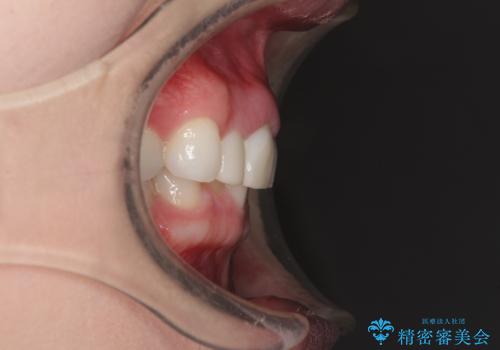

クラウンの状態は、根管治療の状態も含めて決して良い状態とは言えず、矯正治療後の根管治療と補綴治療の再治療を前提として、インビザラインによる矯正治療を行うこととしました。

治療前、下顎前歯はほとんど見えない咬み合わせでしたが、矯正治療によりディープバイトが改善されました。

矯正治療中に前歯2本のクラウンは外れてしまい、途中仮歯に替える必要があったので期間は掛かりましたが、歯列も整い、負担のかからない咬み合わせを達成することができました。